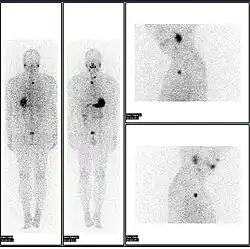

- 2D: Сцинтиграфия (от лат. «знать») — это использование внутренних радионуклидов для создания двухмерных изображений.

Сканирование костей всего тела с помощью ядерной медицины. Сканирование костей всего тела в ядерной медицине обычно используется для оценки различных патологий, связанных с костями, таких как боли в костях, стрессовые переломы, доброкачественные поражения костей, инфекции костей или распространение рака на кость. -

Сканирование паращитовидной железы с помощью ядерной медицины демонстрирует аденому паращитовидной железы, прилегающую к левому нижнему полюсу щитовидной железы. Вышеупомянутое исследование было выполнено с одновременной визуализацией технеция-сестамиби (1-я колонка) и йодом-123 (2-я колонка) и методом вычитания (3-я колонка). -